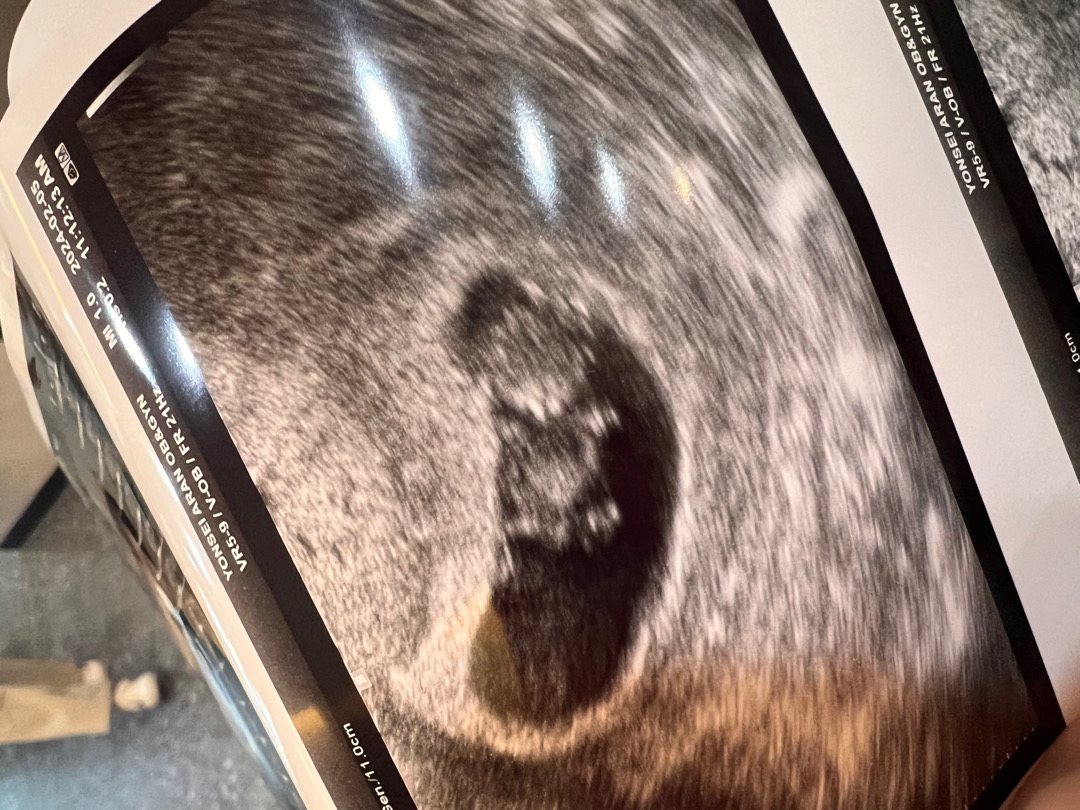

(9주4일) 드디어 젤리곰!!! 활발한 선물이👶🏼

9주4일 크기 2.58cm 심박수 164bpm 입덧이고 머고 아무증상이 없어 불안하고 궁금했는데 너무 건강히 잘 있다는 말 듣고 안심되었어요🙏🏾 1주일 사이 0.5cm나 컸어요!!😁 👱🏽♀️=저,👩🏻⚕️=의사쌤 👱🏽♀️쌤 애기가안움직이네요ㅠㅠ 👩🏻⚕️그건 애기마음이에요 잘수도있구.. (말씀하자마자) 어머 움직이네요 ㅎㅎ 엄마말 들었나봐요 듣자마자 움직이네요 👱🏽♀️어머..너무신기해요 ㅋㅋㅋ귀여워요 👩🏻⚕️ 이때만 볼수있는 젤리곰이에요 ㅎㅎ (다른 아가들 촘파보고 9주정도되면 움직이덬데 선물이는 안움직이길래 여쭤봤어요ㅎㅎ) 말이끝나기무섭게 마구마구움직여주는 선물이😁😁 손도 이리와 할때처럼 까딱까딱 거리고.. 너무너무 너무신기했어요 벌써부터 이러케 활발하면 나중에 태동느낄때 잠 못자는거 아닐까 싶을정도로 엄청 활발하더라구요 ㅎㅎ 이벤트도 많았지만 잘 성장하고있는 아이보니 너무 설레네요ㅠㅠㅠ 우리모두 아이만날 그날까지 힘내요!!!